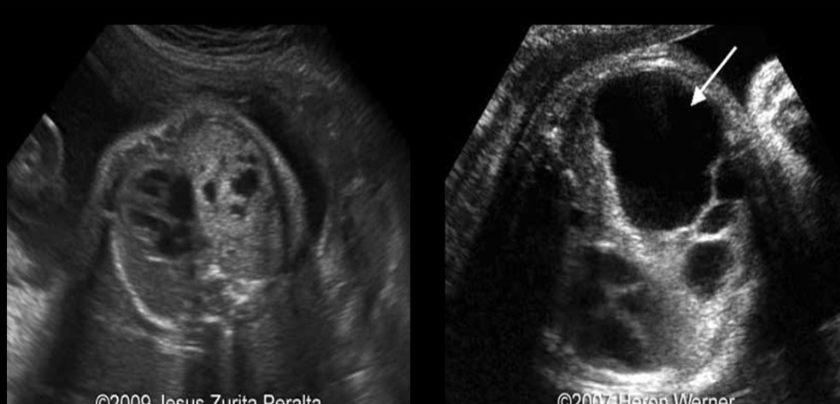

a) type 1 congenital cystic adenomatoid malformation

b) diaphragmatic hernia left side

c) diaphragmatic hernia right side

d) left lung agenesis